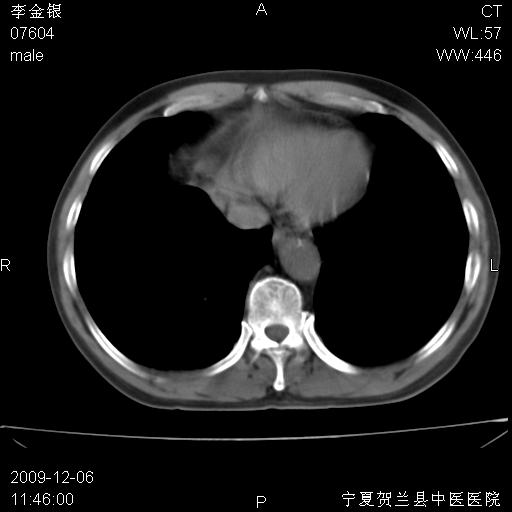

该病人 ,男,62岁,主因咳痰带血两天

考虑右肺中央型占位性病变并阻塞性肺炎.(右肺上叶支气管变窄),建议支纤镜检查.

考虑右肺中心型肺癌伴阻塞性肺炎及右肺门淋巴结转移,建议纤维支气管镜进一步检查。

支气管壁明显增厚 管腔狭窄,腔静脉后多个淋巴肿大,结合年龄病史考虑右肺上叶中央型肺癌并阻塞性肺炎

右肺上叶后段支气管阻塞,右上肺门占位,相应肺段阻塞性肺炎,右肺门有淋巴结肿大。诊断右肺上叶中心型肺癌,阻塞性肺肺炎、右肺门淋巴结转移。

右上叶支气管狭窄,管壁增厚,远端斑片状软组织影,病灶邻近叶间裂,叶间裂无移位。

诊断右肺中央型肺癌。

那个片影应该大部分都是病灶,病灶沿肺段支气管分支生长,后段完全显示不清、闭塞。若为不张应该伴有叶裂的移位,若为炎症应有空气支气管征。

右肺中心型肺癌伴阻塞性肺炎及右肺门与纵膈淋巴结转移很典型,可纤维支气管镜进一步检查

考虑右侧中央型肺癌伴右肺上叶后段阻塞性炎症、肺不张、右肺门和纵隔淋巴结肿大。

右肺上叶中心型肺癌,阻塞性肺炎、右肺门和纵隔淋巴结转移。